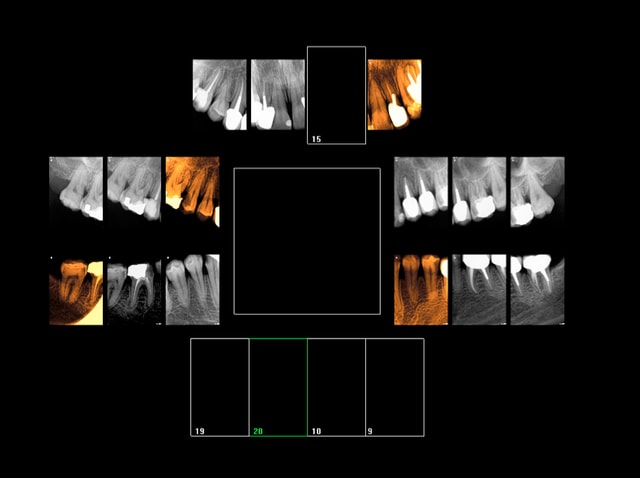

Rebelote aujourd'hui. Pulpite sur 15.

Re re belote. pulpite 38. -))))

Pas venu depuis 2007 date de la pose d'onlays sur 45 46.

On va pas refaire le débat, mais ou bien je suis un mutilator, ou bien je suis lobotomisé, mais il ne me semble pas aberrant de poser IC/Cr sur cette 15 non ?, je me vois pas y coller un onlay.

Après Chicot, on a les mêmes qui consultent quand ça picote sérieux, et en général l'indication du coiffage MTA,biodentine/inlay/onlay, n'est plus vraiment d'actualité.

En général c'est déjà limite pour la couronne alors ...

Suivant : 47 pétée en distal mais pas de douleur ( dernier RDV 2008) . Chiotte elle pouvait pas attendre un peu avant de péter ? j'aime bien les actes qui solvabilisent à la fois le patient et le praticien pas ces soins opposables à un tarif de merde. -)))

Ah ! enfin une endo au résultat non aléatoire sur 36 ! spéciale dédicace pour améli ! -))))

Suivant : 45 cassée ( jadis un onlay support de bridge ? ) Dent gardée vivante puis endo à travers l'onlay je suppose. ca marche moins bien après forcément. -))))

Maintenant la question que je me pose , vais je continuer à soigner les caries moyennes révélées ailleurs par les radios ? Vu qu'on nous prend pour des cons, hein ?

En plus faire les radios et les coter c'est prendre le risque de se faire emmerder par un CDC, autant ne plus en faire non ? ca résoud le problème de conscience que je pourrais me poser à l'avenir ! Il suffira d'attendre les signes d'appels et d'avoir des stocks de R25 ! -))))

Suivant : douleurs 36. Abcès du à un Syndrome du septum dent vivante, dommage.......-)))))

Dernier rendez vous chez le dentiste : 12 ans ( extractions des sagesses)

Notez l'indication des rétro coronaires et de la rétro alvéolaire dans ce cas : pas d'antécédents de soins intensifs et atteinte pulpaire suspectée ( élimination d'un 4ième degré, fais le test au froid après) . -)))))